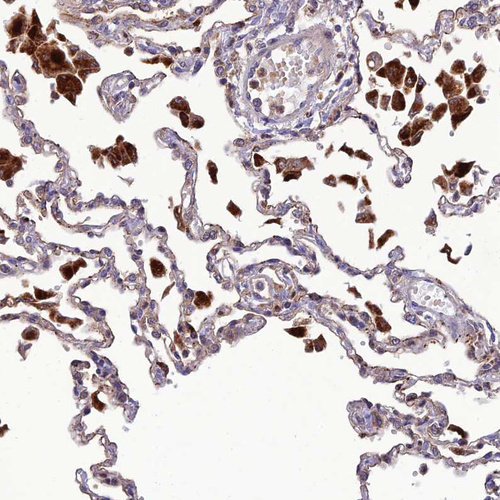

Immunohistochemical staining of human lung shows strong cytoplasmic positivity in macrophages.